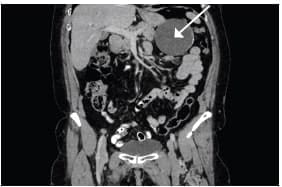

Se realizó una ecografía de abdomen total que informó una imagen quística de 8 x 7 cm, en íntimo contacto con la cola del páncreas. Posteriormente una tomografía computarizada de abdomen con contraste reportó una lesión hipodensa de aspecto quístico, de 86,6 x 78,5 mm, en contacto con la curvatura mayor del estómago, el cuerpo y la cola del páncreas, con paredes irregularmente engrosadas y calcificaciones periféricas aisladas en su interior.

Como primera posibilidad se sugirió un tumor del estroma gastrointestinal (GIST, por sus siglas en inglés) (figuras 1 y 2). La endoscopia de vías digestivas altas diagnosticó una gastropatía antrocorporal no erosiva sin hallazgos patológicos adicionales.

Figura 2. Corte coronal de la tomografía computarizada de abdomen

donde se señala la lesión hipodensa de aspecto quístico.